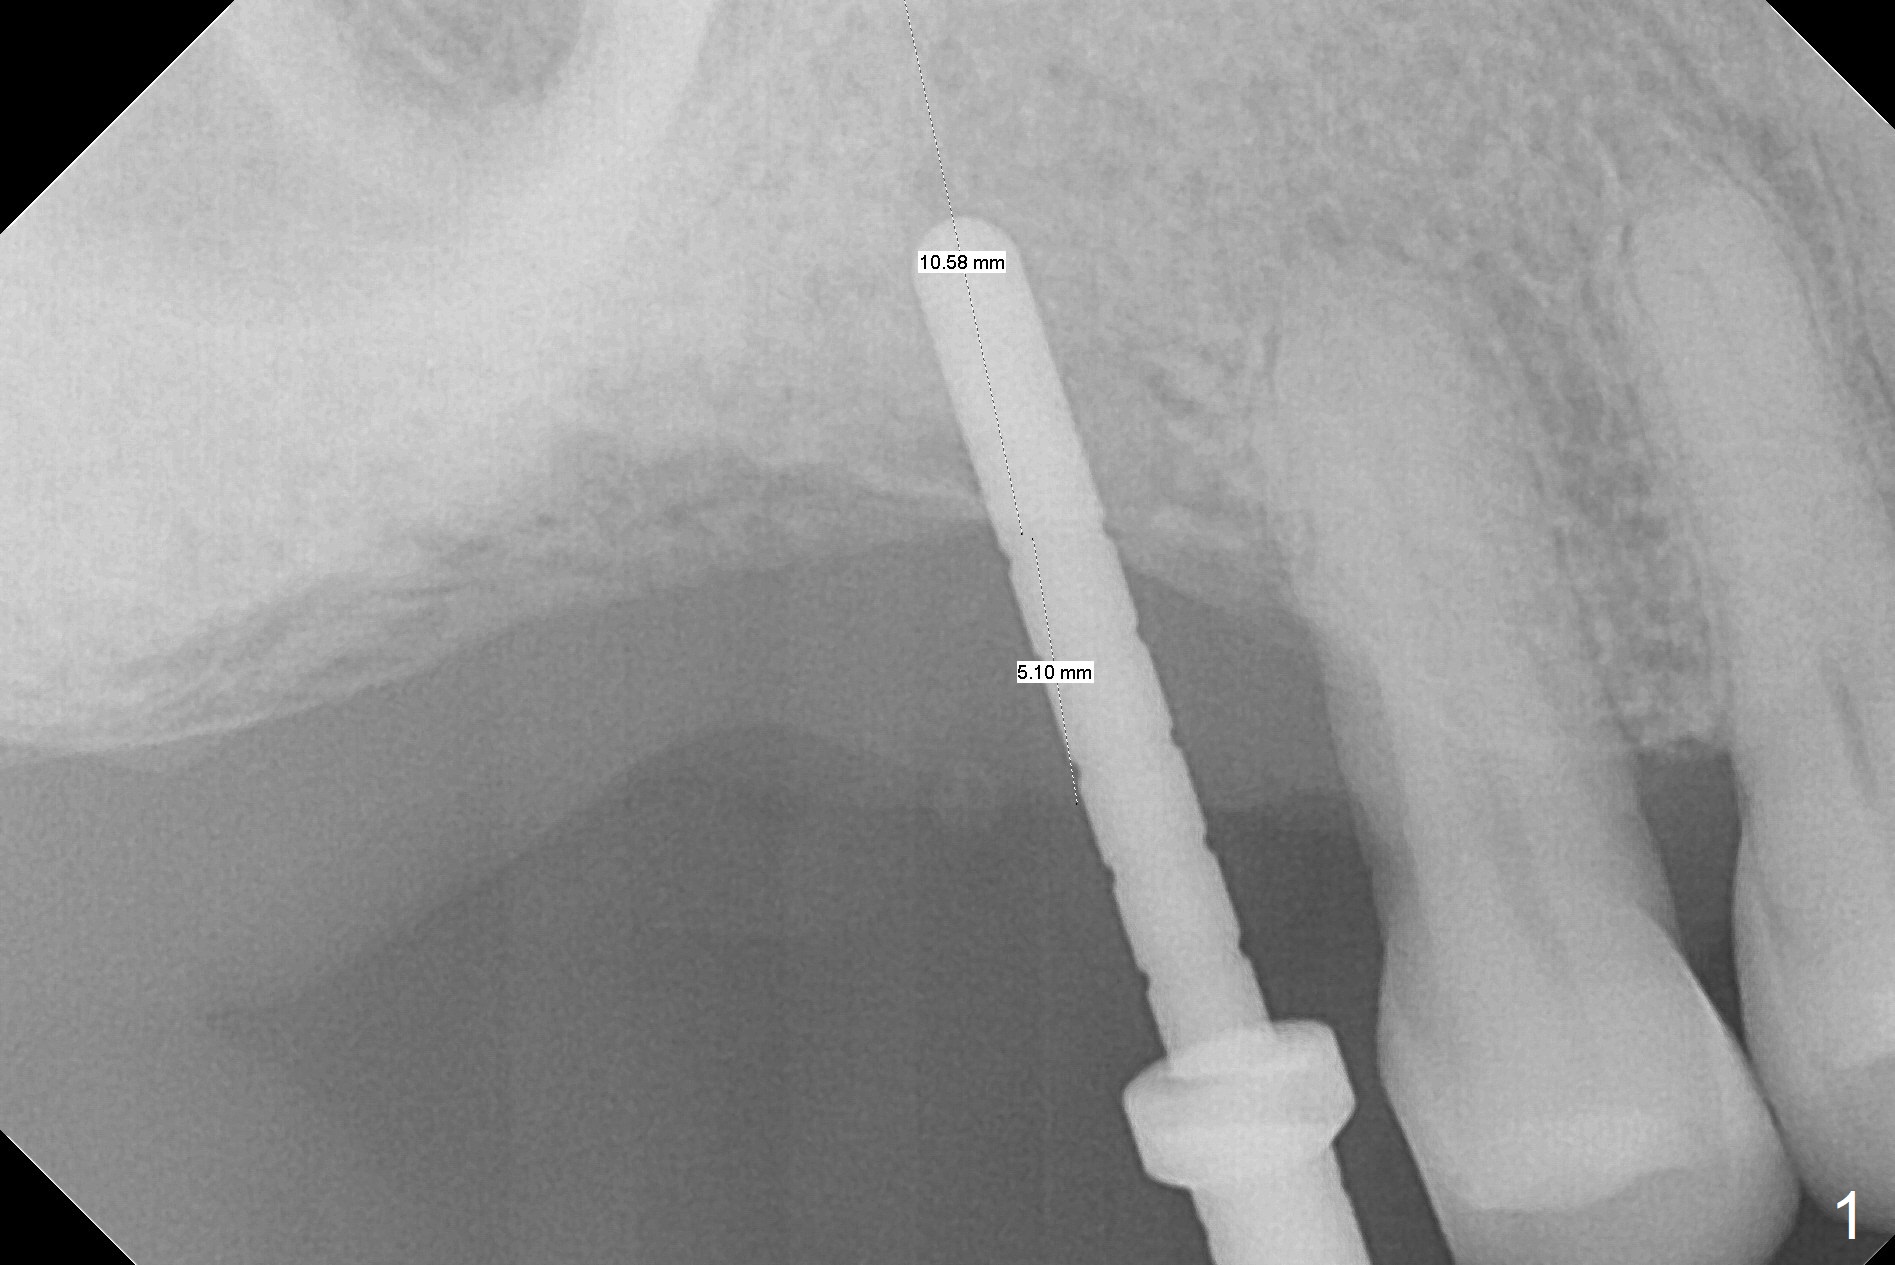

Since the ridge crest at #3 is narrow, Tatum bone scalpels are used to get access and initiate bone expansion, followed by bone blades and RT 2.  It seems that the osteotomy starts mesially; bone height being increased (Fig.1).  When the apical end of the osteotomy tilts mesially, more bone height is obtained.  Drills are alternatively applied because of the hard bone (Fig.2).  A 4x13 mm UF implant is placed initially with the distal threads unburied (Fig.3, >50 Ncm).  With further seating of the implant, a 5.5x5(4) mm abutment is used (Fig.4), which closes the access.  No suture is warranted.  An immediate provisional is fabricated for the patient's comfort and psychological effect.  In fact, the abutment cuff changes to 5 mm prior to temporarization.  There appears no bone loss <4 months postop (Fig.5).  Pulpitis develops at #4 due to DO caries 1 year 5 months post cementation (Fig.6 *).  The crown at #3 is removed for easy and conservative distal carious removal and Cavit temporary restoration to prevent sodium hypochlorite leakage.  Then occlusal access is made for pulpotomy.  When RCT finishes, no crown will be made, but occlusal reduction is required.    The patient returns for RCT 1 month later (Fig.7,8). Cavit remains in place (Fig.7 C).  Although 2 threads are exposed distal (Fig.8 arrow), there is no sign or symptom of periimplantitis, which may be related to the thick gingiva (arrowhead).  Return to Upper Molar Immediate Implant, IBS, #14 (Tissue Punch) Xin Wei, DDS, PhD, MS 1st edition 08/25/2017, last revision 09/08/2019